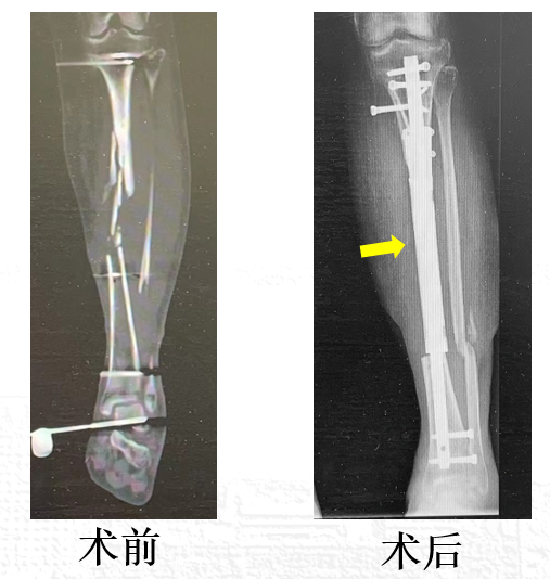

在专业的功能锻炼下,目前,林女士已经能够通过辅助进行负重行走。复查X线显示,3D打印假体稳定,整体恢复顺利。

图4 患者手术前后影像学检查对比